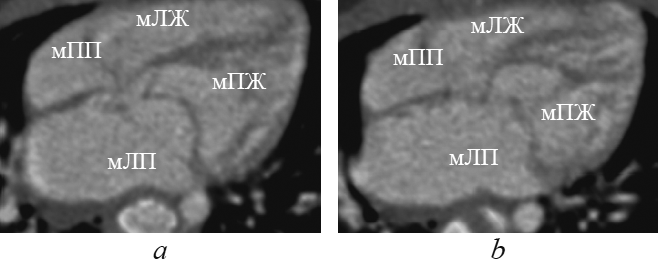

При корригированной транспозиции магистральных артерий морфологически правый желудочек располагается слева и сзади от морфологически левого желудочка (рис. 5, 6).

Рис. 5. Реформация приточных отделов желудочков при корригированной транспозиции магистральных артерий. мЛЖ — морфологически левый желудочек; мЛП — морфологически левое предсердие; мПЖ — морфологически правый желудочек; мПП — морфологически правое предсердие

Fig. 5. Supply ventricles division reformation in corrected great arteries transposition. мЛЖ – morphologically left ventricle; мЛП – morphologically left atrium; мПЖ – morphologically right ventricle; мПП – morphologically right atrium

Рис. 6. Реформация приточных отделов желудочков при корригированной транспозиции магистральных артерий. мЛЖ — морфологически левый желудочек; мЛП — морфологически левое предсердие; мПЖ — морфологически правый желудочек; мПП — морфологически правое предсердие

Fig. 6. Supply ventricles division reformation in corrected great arteries transposition. мЛЖ — morphologically left ventricle; мЛП — morphologically left atrium; мПЖ — morphologically right ventricle; мПП — morphologically right atrium